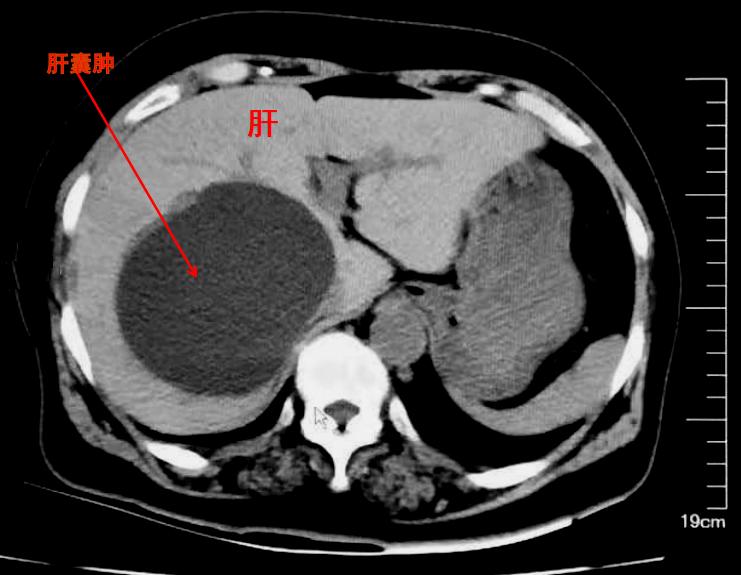

肝囊肿,并不是肿瘤

举一些实例来看:囊肿、血肿、肉芽组织增殖等,都不是肿瘤,但却通常表现为肿块,在前面的病例中,小李的腕部所摸到的腱鞘囊肿,就表现为肿块,但却并不是肿瘤(有时也被称为肿瘤样病变)。